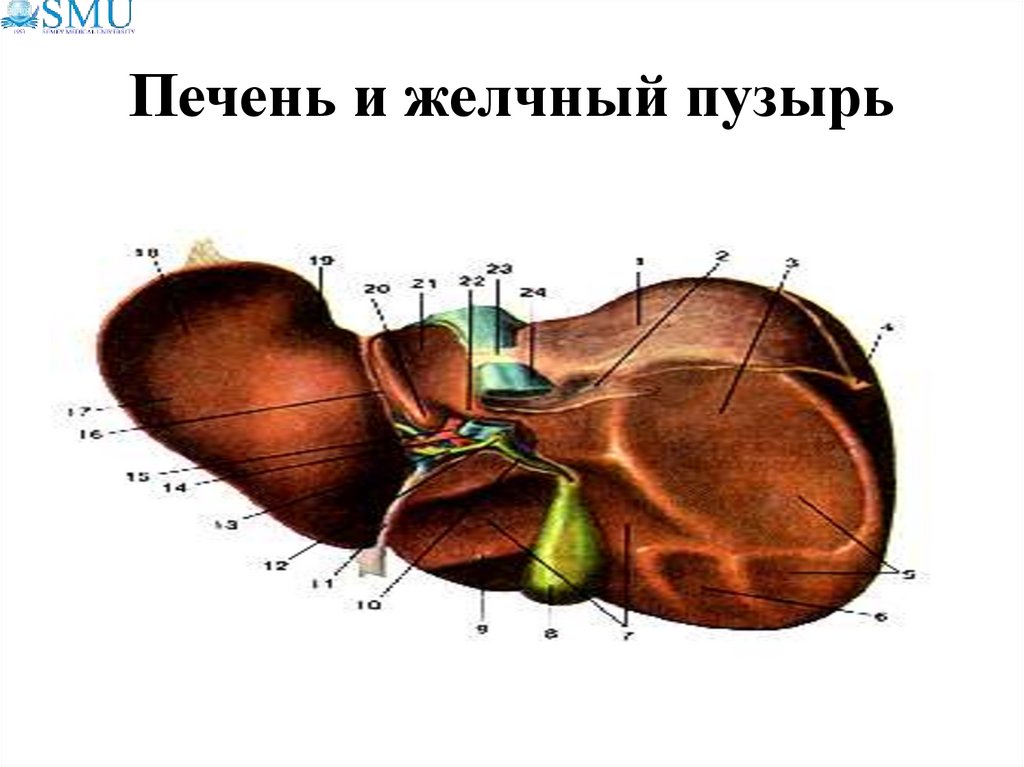

Анатомия и особенности Гартманова кармана желчного пузыря